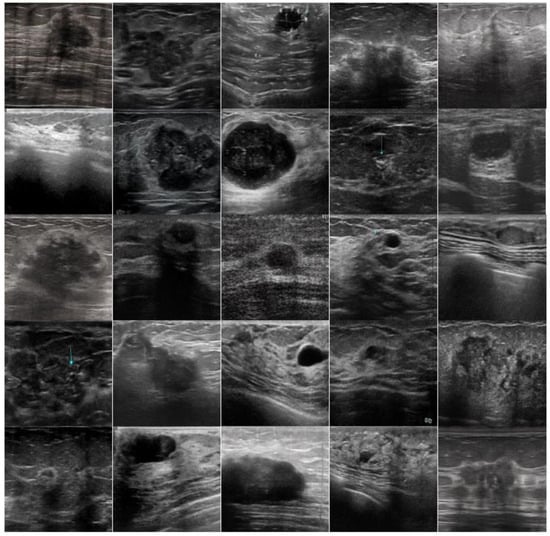

The foundation of this research was a dataset comprised of 3186 ultrasound images of breast lesions, collected from four different publicly available sources, including breast lesions ultrasound (BrEaST), BUSI, Thammasat, and HMSS (Figure 2). The images were categorized into two groups, malignant and benign, according to the clinical annotations provided. Our study was underpinned by an extensive analysis of ultrasound images of breast lesions, classified as malignant or benign. To achieve the most accurate and generalizable results, a comprehensive dataset was compiled from various sources. This process ensured a broad spectrum of characteristics and features in the ultrasound images, which is necessary for training and testing deep-learning models.

• BrEaST-Lesions USG—offers a collection of ultrasound images of breast lesions, equipped with detailed annotations, including clinical data and histological analysis results. We have utilized 252 images from this dataset, including 154 benign types and 98 malignant types [34].

• Dataset BUSI with GT—includes breast ultrasound images with precise demarcation of tumor boundaries, providing valuable data for training recognition and classification models. From this dataset, we have utilized 454 benign cancers and 211 malignant cancers, giving a total of 665 images [35].

• Thammasat University Dataset—contains images gathered by researchers at Thammasat University, including images with various artifacts, contributing to model training in conditions close to real clinical practice. From this open-source dataset, we have utilized 2006 breast ultrasound images, including 846 benign and 1160 malignant lesions [9].

• HMSS Ultrasound Cases—provides an extensive collection of ultrasound diagnostic cases, including images of breast formations, enriching the dataset with a variety of cases. From this dataset, we have used 263 images, in which 120 are benign and 263 are malignant [36].

Figure 2. The distribution of breast ultrasound images by pathology types across the datasets.